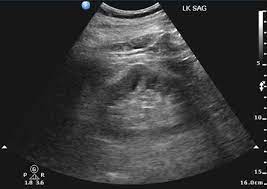

Dromedary Hump - Dromedary Hump Nephropocus : The term dromedary hump or splenic hump refers to a bulge in the middle of the lateral surface of the left renal cortex.. Dromedary humps are prominent focal bulges on the lateral border of the left kidney.they are normal variants of the renal contour, caused by the splenic impression onto the superolateral left kidney. Bactrian camels have two humps, while the dromedary camels have only one hump on their back. 1 , 2 it is named. The term dromedary hump or splenic hump refers to a bulge in the middle of the lateral surface of the left renal cortex. Dromedary hump is a radiological term for normal kidney tissue molded by the adjacent organs.

Dromedary hump appears as a focal bulge on the lateral border of the left kidney, caused by molding of the normal renal parenchyma by the adjacent spleen.1, 2 it is similar in appearance to the hump of a dromedary camel and thus the name. A dromedary and its child, two hours old. Apart from the differences in the number of humps, there are other notable differences too. Hello, i'm marcelo from brazil. Bactrian camels have two humps, while the dromedary camels have only one hump on their back.

Dromedary hump appears as a focal bulge on the lateral border of the left kidney, caused by molding of the normal renal parenchyma by the adjacent spleen. A dromedary has one hump, long limbs and short hair. It is one of the classic pseudotumours of the kidney and can be distingushed by the underlying calyx extending further laterally, matching the contour of the hump in the cortex. Dromedary hump and bertini columns are two of the renal pseudotumors. Dromedary camels live in hot climates. = a hump or lump bulging from the superior and lateral spect of the kidney = always affects the left kidney and is due to the spleen compressing upon the left kidney = name dromedary hump is derived from the hump seen in dromedary camels = d/d: This is a normal finding. Since this looks like camel's hump on the film, this is called dromedary hump. Care should be taken as it can be mistaken for a renal mass. The incidence of this normal anatomic variant is estimated to be about 0.5%.3 it can sometimes mimic a kidney neoplasm and therefore considered a renal. 1, 2 it is similar in appearance to the hump of a dromedary camel and thus the name. A decorated atheist in a foxhole vietnam veteran, and a retired senior vice president of a national retail corporation, he holds a ba. Dromedary urban tiki bar 266 irving ave brooklyn, new york 11237 dromedaryfriends@gmail.com.

The main difference between a camel and dromedary lies in the number of humps they have on their back. Dromedary camels are the tallest. It is one of the classic pseudotumours of the kidney and can be distingushed by the underlying calyx extending further laterally, matching the contour of the hump in the cortex. For instance, the length and thickness of their fur differ. It is usually created by the pressure of surrounding organs to the cortex of the kidney during development. Dromedary hump appears as a focal bulge on the lateral border of the left kidney, caused by molding of the normal renal parenchyma by the adjacent spleen.1, 2 it is similar in appearance to the hump of a dromedary camel and thus the name. The incidence of this normal anatomic variant is estimated to be about 0.5%.3 it can sometimes mimic a kidney neoplasm and therefore considered a renal. The dromedary hump (dh) is marked along the lateral border. The bactrian lives in cold climates. Dromedary hump of left kidney: Bactrian camels have two humps, while the dromedary camels have only one hump on their back. On june 4, 1855, major henry c. Dromedary hump is a radiological term for normal kidney tissue molded by the adjacent organs.

Dromedary hump appears as a focal bulge on the lateral border of the left kidney, caused by molding of the normal renal parenchyma by the adjacent spleen1, 2 it is similar in appearance to the hump of a dromedary camel and thus the name drome. Since this looks like camel's hump on the film, this is called dromedary hump.